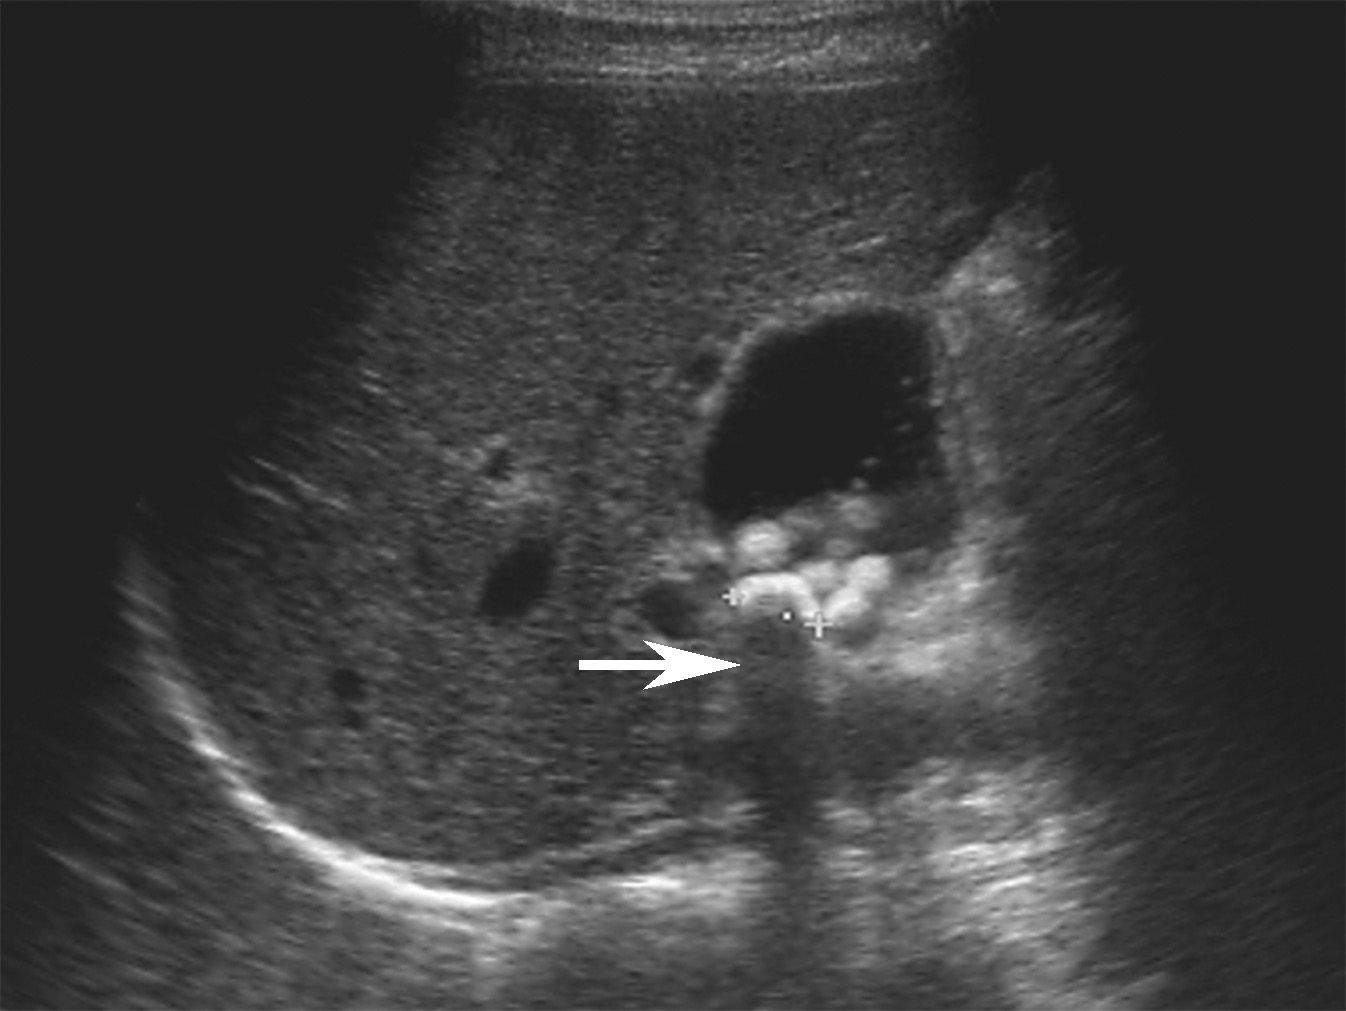

2)强回声结石后方伴声影(图2-6-2),结石的声影边缘锐利,宽度与结石的宽度基本一致,此特征可与胃肠气体形成的声影相鉴别。

图2-6-2 典型胆囊结石灰阶超声图像

箭头所示为声影